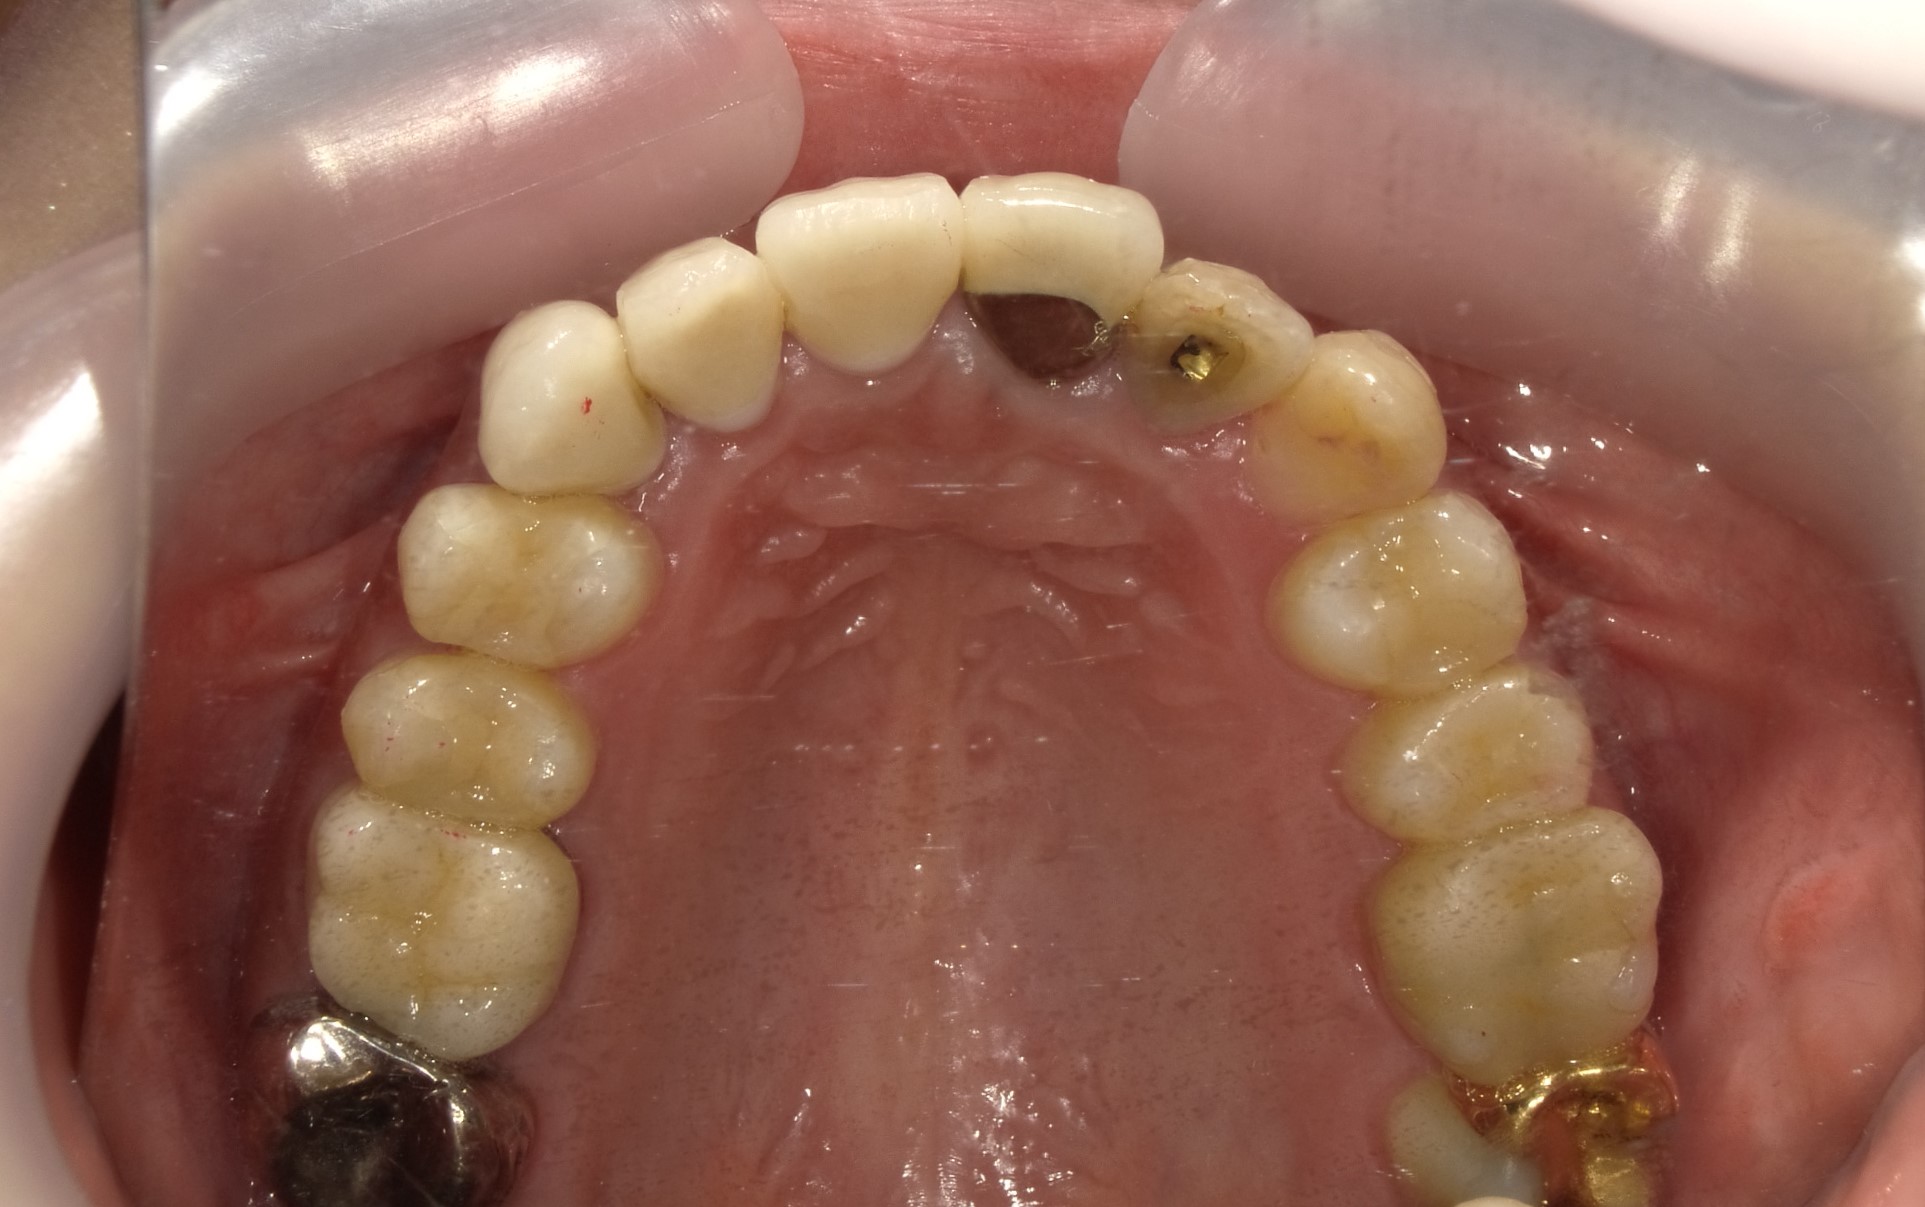

◾️治療後の状態(After)

インビザライン矯正により、前歯の歯の重なりが解消され、犬歯を含む前歯が歯列内にきれいに収まりました。

歯列のアーチも整い、八重歯による突出感も改善しています。

◾️治療内容の概要

治療方法:マウスピース型矯正装置(インビザライン)

治療期間:8ヶ月

◾️矯正治療に伴うリスク・注意点

歯列矯正中に伴う疼痛・咬合痛・う蝕・歯肉退縮などのリスクがあります。治療期間や費用については個人差があります。